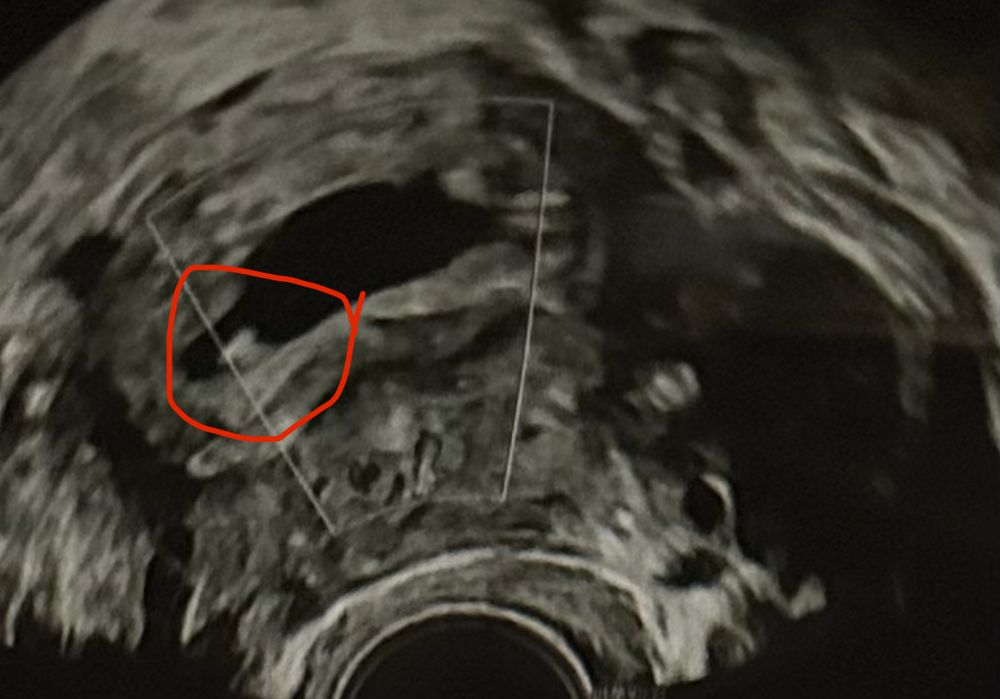

Здравствуйте девочки - вопрос возможно глупый но ситуация странная. Итак, в прошлую субботу мне исполнилось 3 недели после 5-дневного переноса эмбрионов. Итак, сканирование показало эмбрион размером 1,9 мм и плодное яйцо диаметром 9,5 мм. Я сдавала ХГЧ 4 раза за этот период и все в порядке. Вчера сделала сканирование (то есть через 4 недели после переноса) и уже виден только мешок 15,3 мм, а эмбрион исчез? Может ли быть такое - одну неделю эмбрион существует, а вторую неделю чудесным образом исчезает? У меня не было ни кровотечения, ни болей в животе. Прикрепляю фото первого скана с эмбрионом и второго вчерашнего скана без эмбриона. Врач рекомендовал мне продолжить лечение до следующего четверга и сделать еще одно сканирование через 5 недель после переноса. Любые предложения и советы будут оценены по достоинству. Большое спасибо

Ангелина, и сейчас прикреплю и рапорт где есть эмбрион

Ангелина, и сейчас прикреплю и рапорт где есть эмбрион